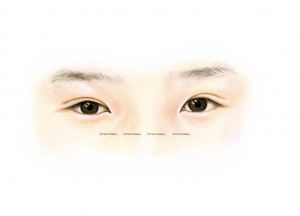

The most commonly performed eyelid surgery in people from East Asia is sometimes referred to as “double eyelid surgery”, and is a cosmetic surgical method that reconstructs the skin of the upper eyelid. Often oculoplastic surgeons also partially remove any skin surplus, which is a natural consequence of ageing. We oculoplastic surgeons can also create an eyelid crease – something that is naturally missing in people from East Asia (which is sometimes referred to as a “mono-lid”).

Postoperative image.